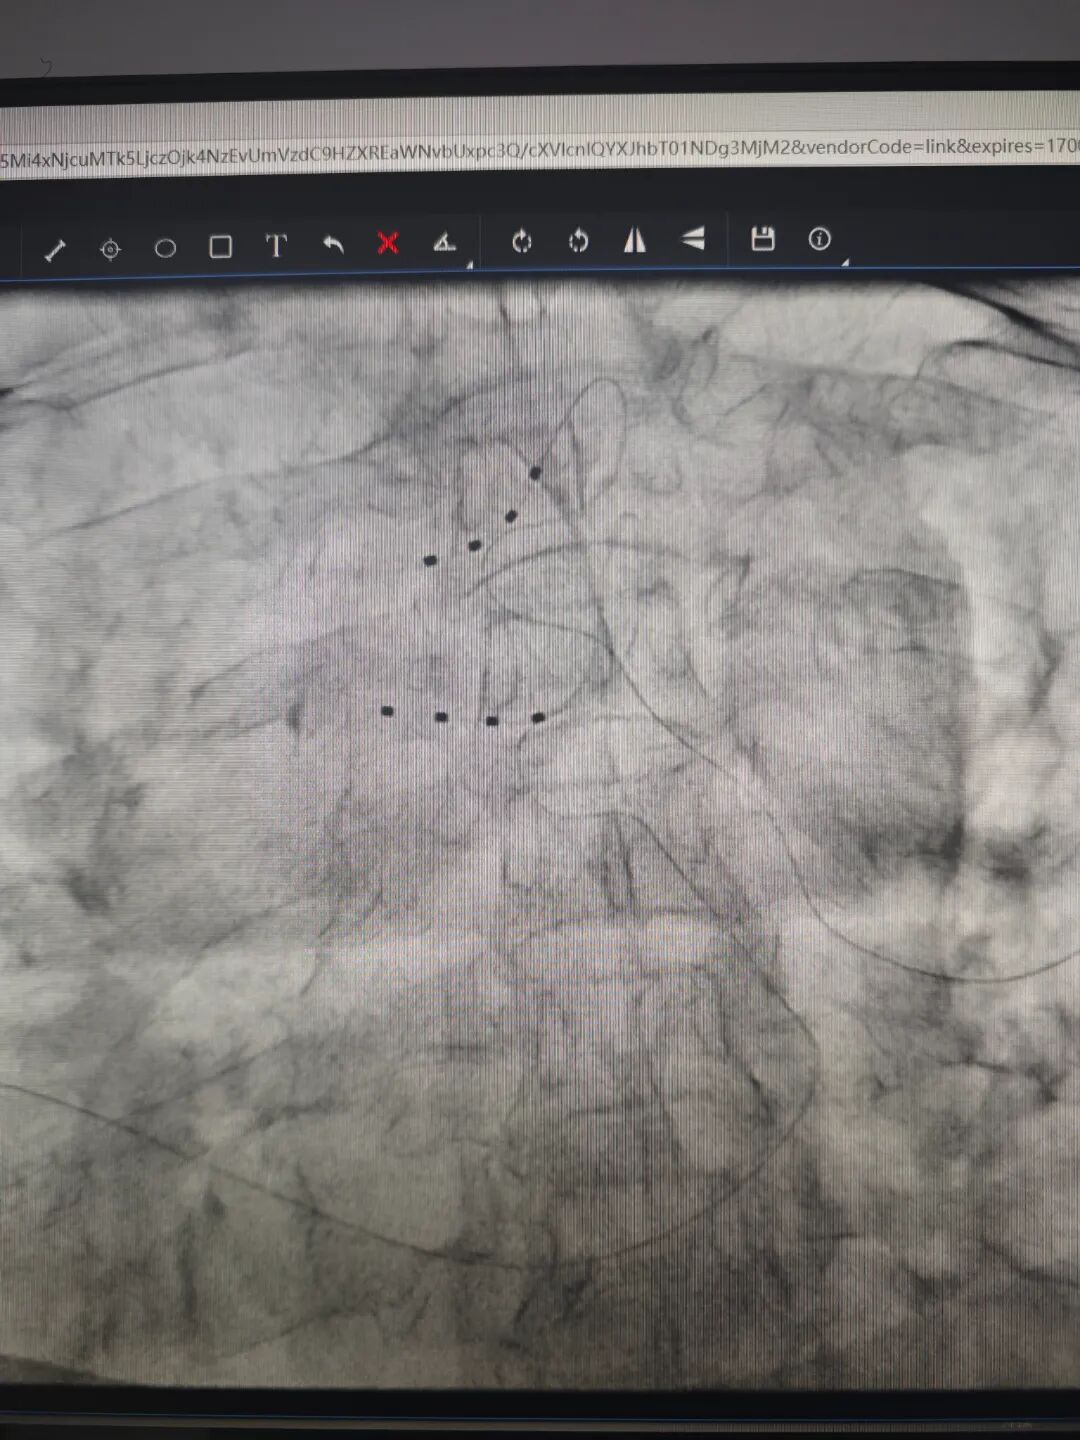

收入院后,经过评估,11月23日,黎哲敏、郑臻医生为姜阿姨进行了背根节电刺激 (dorsal root ganglion stimulation, DRGS),经过一周治疗,姜阿姨的带状疱疹后遗神经痛得到有效缓解,开心出院。

据介绍,背根节电刺激是电刺激治疗方式的一种,类似于脊髓电刺激治疗,该治疗具有刺激精准、副作用小的优势,可以避免神经调节方式的迁移和植入位置产生的副作用。

脊髓电刺激(SCS)是一种安全有效治疗多种类型慢性顽固性疼痛的治疗方法。通过植入脊髓硬膜外腔的电极导线将神经刺激器产生的电流传至脊髓,针对脊神经进行低压电电刺激,阻断疼痛感上传到大脑中枢,达到缓解疼痛的效果。是对带状疱疹急性期疼痛和带状疱疹后遗神经痛均有控制作用。其电脉冲信号可以刺激中枢抑制性神经递质的产生、激动脊髓上位疼痛调节中枢、抑制交感神经的兴奋性等,起到修复、调控受损感觉神经的作用,达到标本兼治的效果。